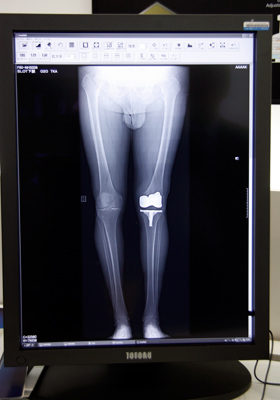

![]() 開発中の新再構成処理法は,金属アーチファクトを抑え,インプラントと骨の境界を明瞭に描出する。 |